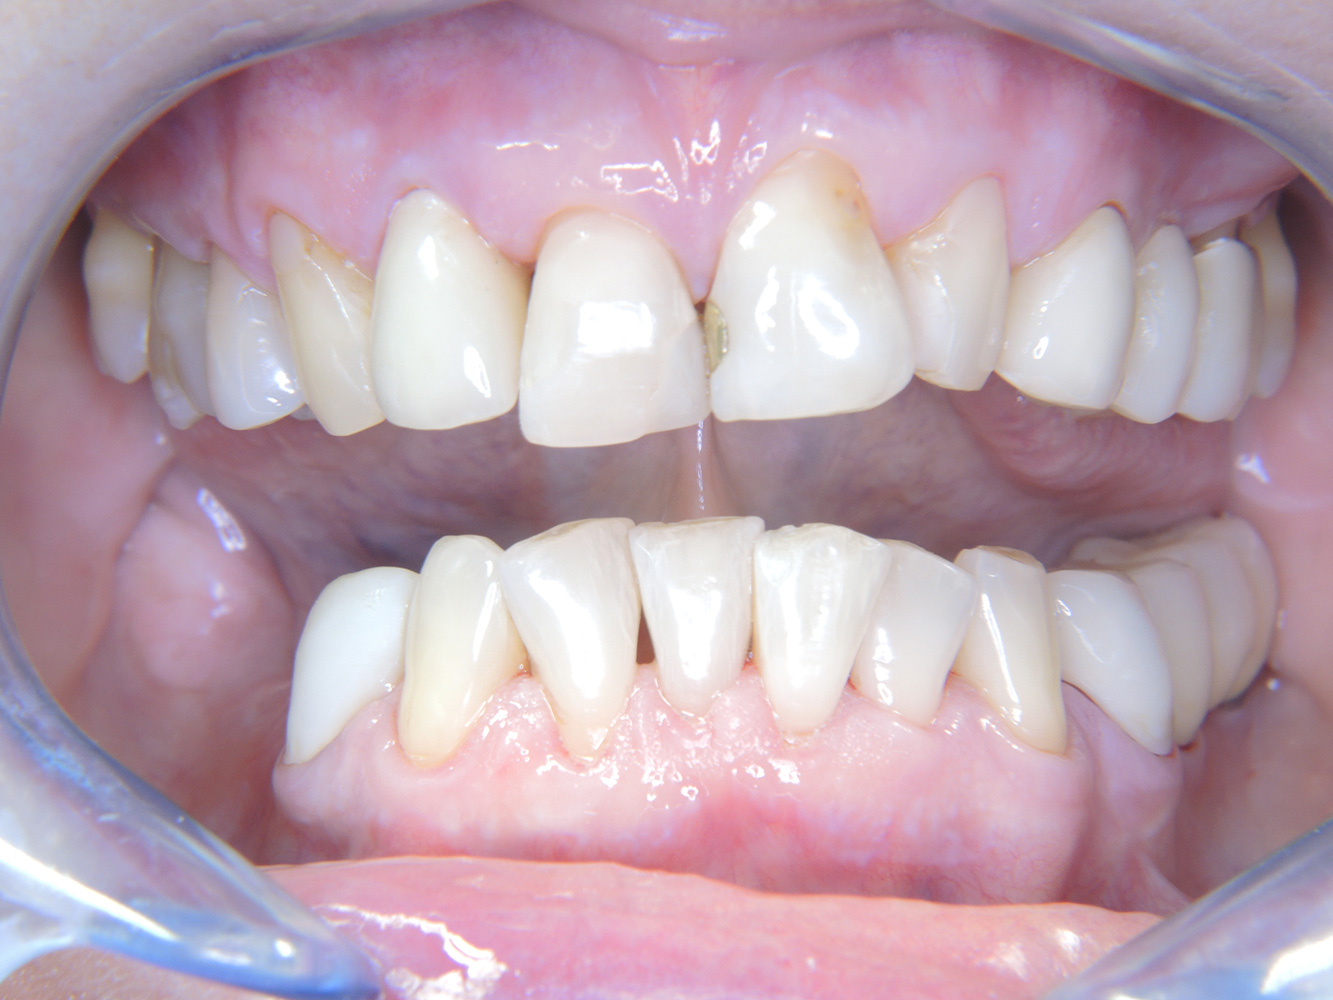

Questa paziente di 68 anni non presenta alcuna patologia precedente né segue alcuna terapia che possano ritenersi rilevanti dal punto di vista odontoiatrico, e il suo stile di vita non comporta alcun rischio particolare. La paziente ha due impianti (3° quadrante, da cinque anni) e una precedente patologia parodontale (parodontite allo stadio IV, grado B) con perdita del dente. Al momento le condizioni parodontali sono stabili, tuttavia la parodontite aumenta in misura significativa le complicazioni biologiche degli impianti e c'è dunque il rischio di perdita dell'impianto (21). Per la seduta di profilassi si possono formulare quattro consigli.